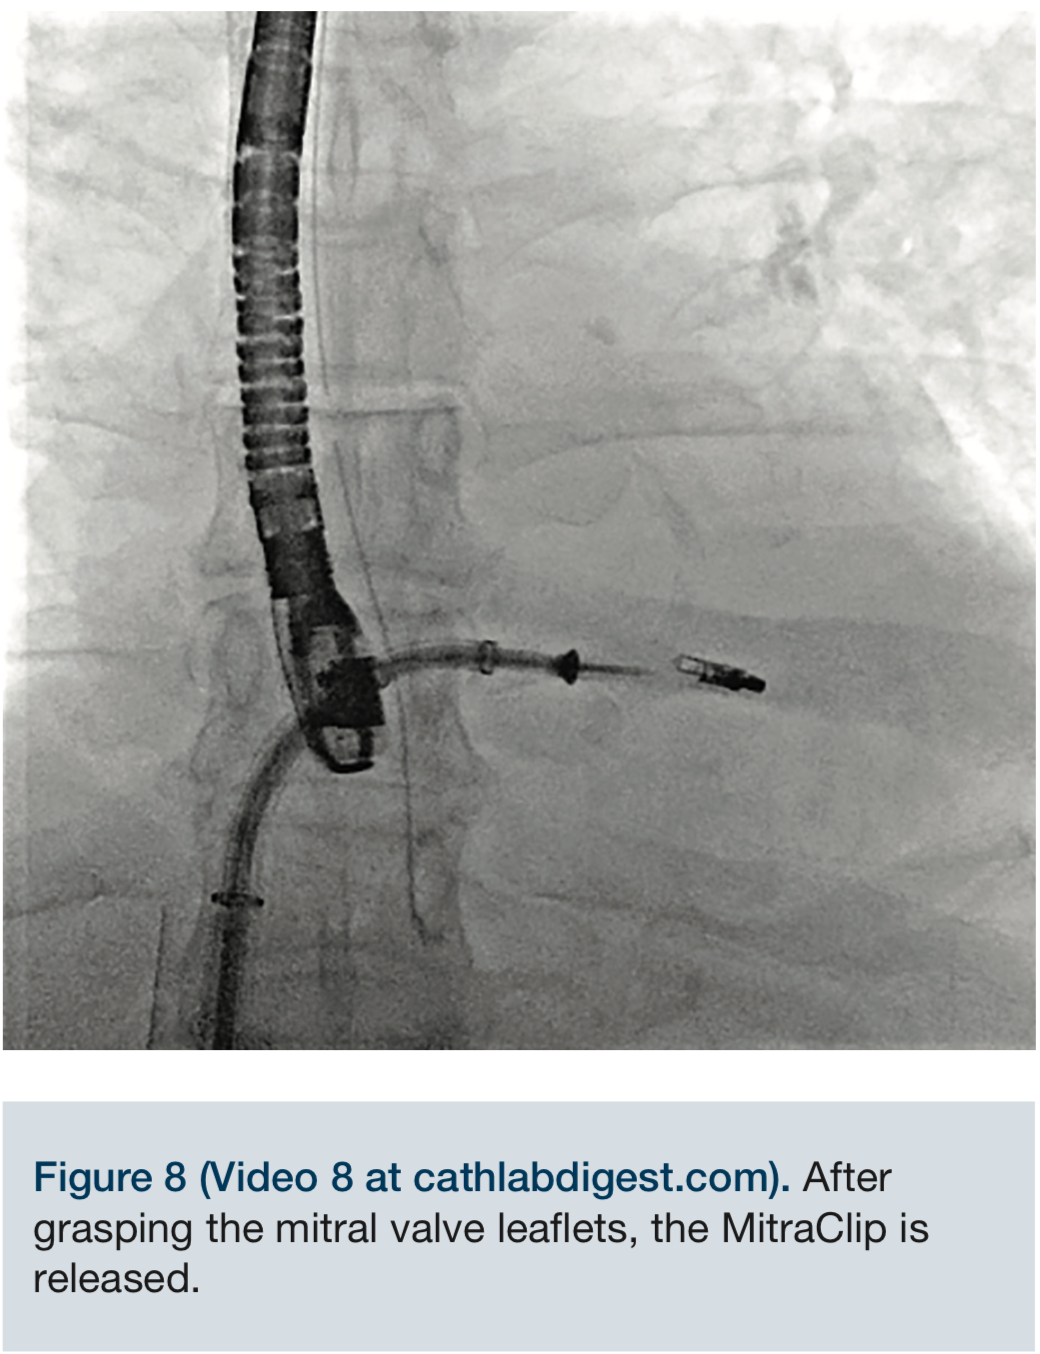

Video 8. After grasping the mitral valve leaflets, the MitraClip is released.

The MitraClip delivery system was then advanced into the left atrium, and the delivery system was placed into a suitable position over the targeted area, under fluoroscopic and echocardiographic guidance. The clip was advanced into the left ventricle and retracted, trapping the leaflets. The mitral regurgitation was evaluated with the clip partially closed and found to be significantly reduced. The regurgitation was essentially eliminated, and the clip was fully closed.

The clip was detached from the delivery system in excellent position. The delivery system was removed from the steerable guide catheter and subsequently, the 24 French sheath was removed. Echocardiographic imaging showed no significant intra-atrial flow or shunt. Completion of the previously placed ProGlide preclosure and figure-of-eight sutures effected right femoral venous hemostasis.